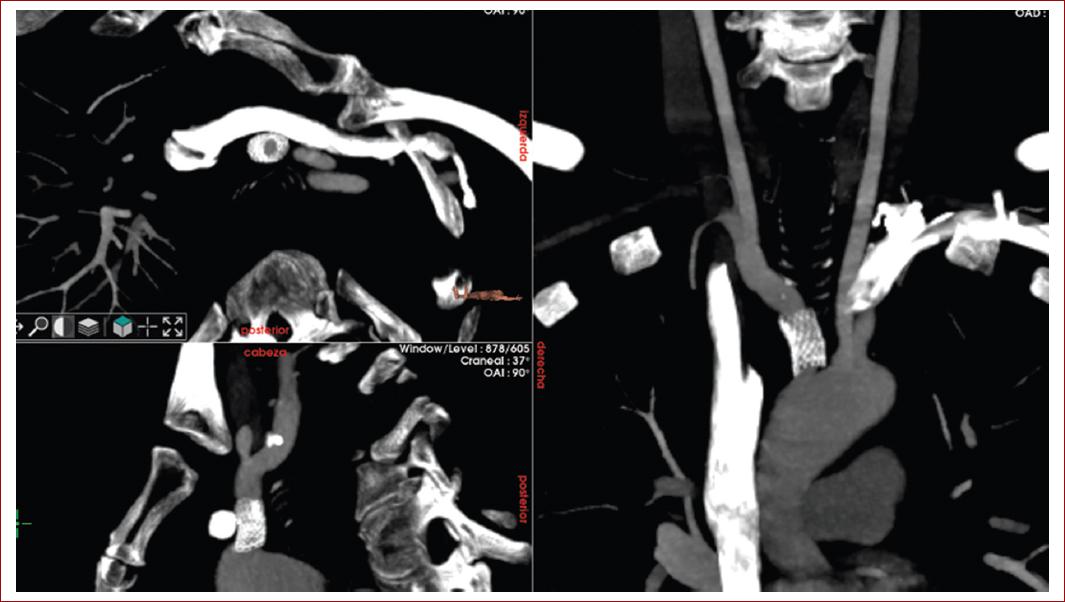

Desde el abordaje femoral se introduce una guía hidrófila de 0.035 × 260 cm angulada (TERUMO® RADIOFOCUS®), se coloca un catéter pigtail centimetrado de 5 Fr en la aorta ascendente y se realiza una aortografía intraoperatoria con bomba de contraste, confirmando una estenosis crítica de TBC. Mediante punción de la arteria carótida común se realiza el abordaje retrógrado del TBC y se sobrepasa la lesión con la guía hidrófila de 0.035 × 260 cm angulada, y un catéter multipropósito de 5 Fr se intercambia por una guía rígida con paso de la misma a la aorta descendente. Se realiza una arteriografía de control para observar tanto los TSA como las ramas aórticas viscerales. Confirmando su permeabildiad, se procede al implante de un stent recubierto expandible con balón de 11 × 29 mm (GORE® VIABAHN®, VBX, Flagstaff, AZ) insinuado en la aorta (Fig. 4). Se realiza dilatación con balón para adaptar el stent a la dilatación posestenótica. Se realiza una arteriografía de control en la que se evidencian el correcto posicionamiento del stent adaptado al diámetro proximal y distal de la zona tratada, la ausencia de estenosis residual y sin complicaciones inmediatas.

Figura 4 Implante de stent recubierto expandible con balón de 11 × 29 mm en el tronco braquiocefálico insinuado en la aorta.

En la revisión en consulta a los 6 meses, el paciente se encuentra asintomático, habiendo utilizado doble antiagregación con ácido acetilsalicílico y clopidogrel. En la exploración física se evidencia que conserva el pulso radial y cubital derecho. Además, no presenta nueva focalidad neurológica y en la angiotomografía de TSA de control se evidencia la permeabilidad del stent, sin imágenes sugestivas de complicación (Fig. 5). La ecografía de control muestra mejoría de la velocidad pico sistólica en la arteria carótida común, la ACI y la arteria carótida externa (Fig. 6).